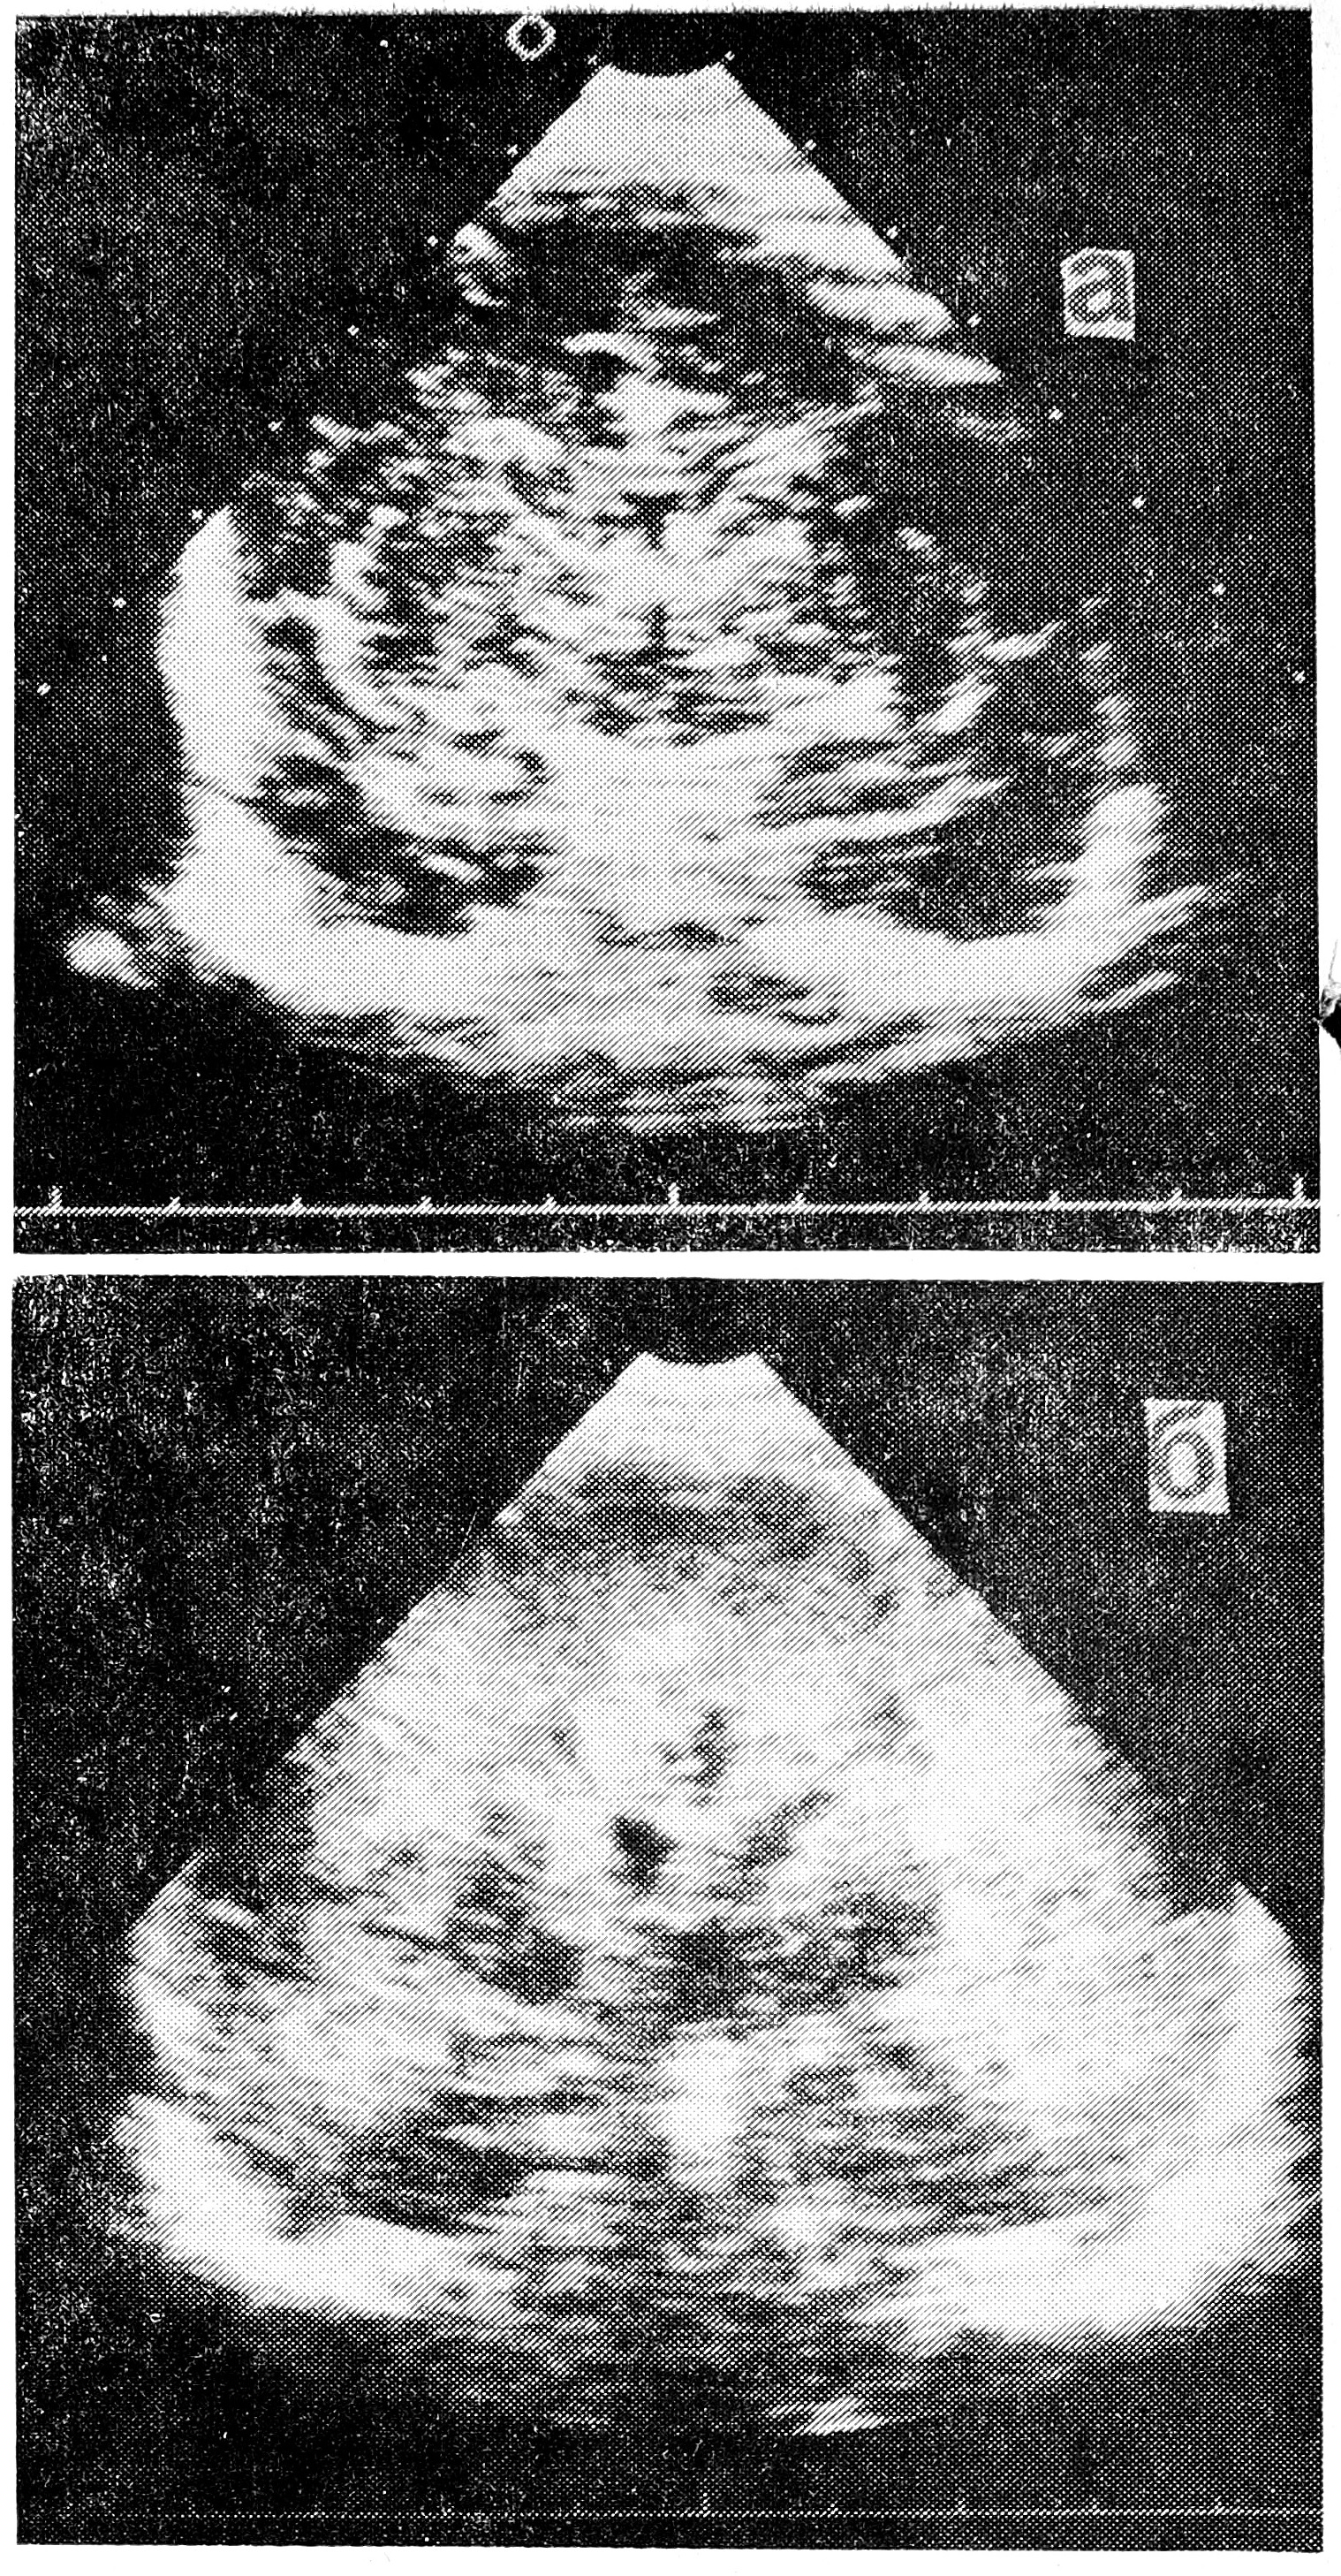

Диагноз герпетического поражения мозга ставился на основании данных клинико-лабораторного обследования (см. табл.). У 1-го пациента диагностирован хронический внутриутробный двусторонний некротический панэнцефалит, у 2-го — внутриутробный двусторонний некротический панэнцефалит, у 3-го — тяжелая постасфиктическая энцефалопатия в сочетании с острым двусторонним некротическим панэнцефалитом, у 4-го — острый подкорковый энцефалит, у 5 и 6-го — острый двусторонний подкорково-стволовой энцефалит с молниеносным течением (с летальным исходом), у 7-го — острый двусторонний субэпендиматит, у 8 и 9-го — острый двусторонний некротический панэнцефалит, у 10-го — острый односторонний диэнцефально-подкорковый некротический энцефалит. В случае острой неонатальной герпетической нейроинфекции, в отличие от внутриутробной, при эхо- энцефалографии в первые дни жизни выявлялась общая или локальная гиперэхогенность вещества мозга (рис. 1). Некротический характер острого энцефалита определялся спустя 2—3 недели после рождения на основании эхографической картины мозга.

Рис. 1. Эхографическая картина головного мозга при остром герпетическом энцефалите: а — эхограмма мозга здорового новорожденного, б — диффузное повышение эхогенности лобных и височных долей больших полушарий у ребенка с герпетическим энцефалитом (2 недели жизни).